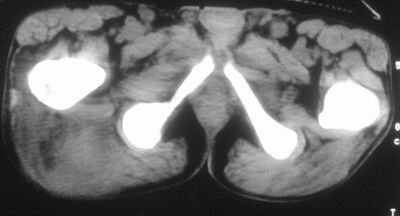

标题: CT16837:M63Y,右臀部巨大软组织包块

患者,男,63岁,自诉3个月前发现右臀部包块,触及疼痛,治疗后缩小。前天突然增大。无高热病史。

考虑-----右臀大肌,臀中肌---感染性病变可能性大。

病灶内部可见出血,首先考虑急性出血性病变.血肿?

给个骨窗,判断一下肿块是否与髂骨有关,肿块内出血是肯定的,至于是感染形成的脓肿还是起源于肌肉或纤维组织的肉瘤则难以确定,不过从影像上看,包膜完整,且环形增厚,病灶下部见斑片状底密度坏死,个人倾向感染可能性大

肌间隙明显混浊,三个月前治疗有缩小,支持考虑臀大肌下脓肿伴出血,肿瘤如果出现瘤内出血的话瘤外边界应该较清楚,现在表现为一种恶性征像,但骨质无明显异常,且臀小肌边界清楚,不符合恶性表现.